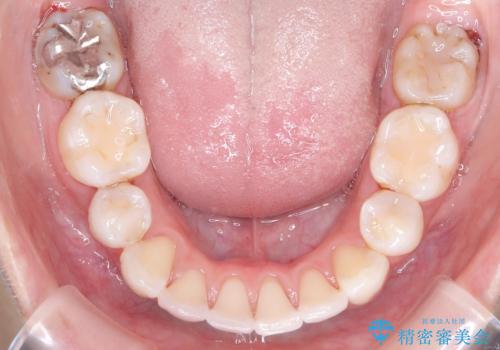

今回の矯正治療では、口元を大きく下げるため、上下左右の小臼歯を抜歯しました。装置には、上顎は歯の裏側に装着する裏側矯正(舌側矯正)を、下顎は透明で目立ちにくい審美ブラケットを使用するハーフリンガル矯正を選択。これにより、治療中も他人の目を気にすることなく、ストレスなく過ごしていただけました。抜歯によってできたスペースを有効活用し、歯列全体を後方へ移動させることで、口元の突出感を解消。治療の結果、口元がすっきりと整い、自信のある美しい横顔を獲得していただけました。